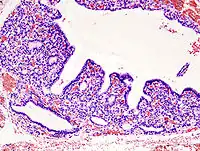

.jpg)